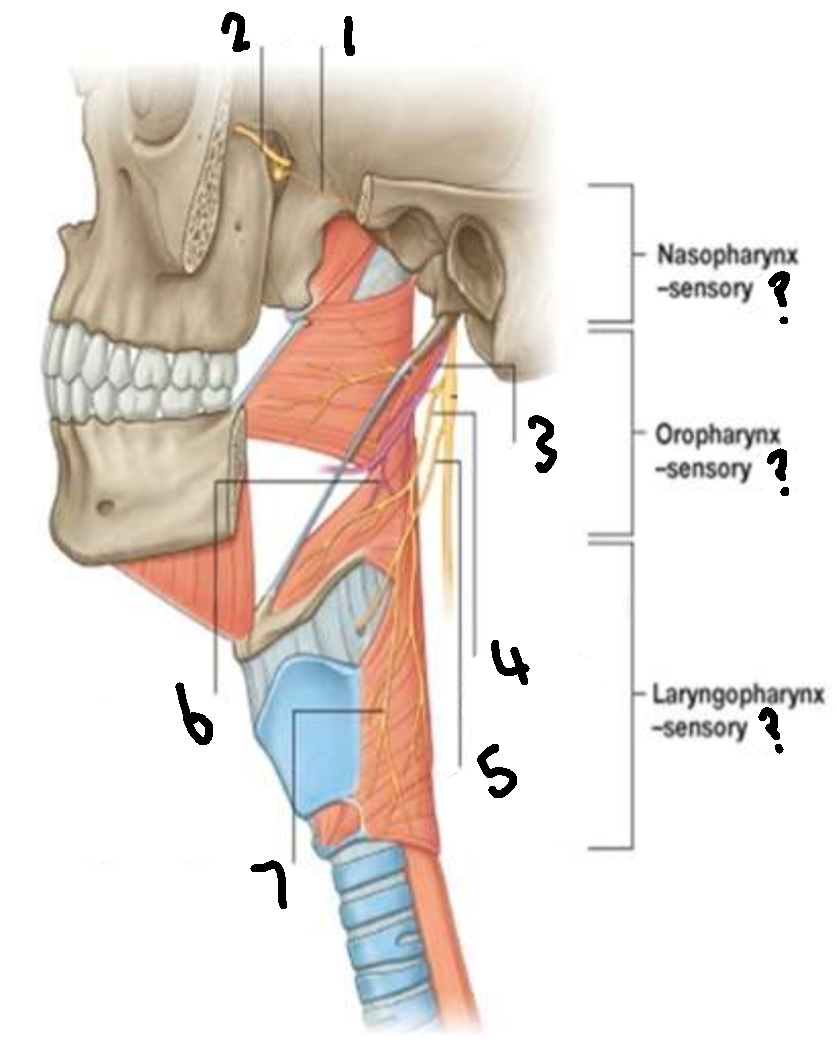

What provides sensory innervation to the nasopharynx?

mandibular branch of trigeminal V2

What provides sensory innervation to the oropharynx?

glossopharyngeal IX

What provides sensory innervation to the laryngopharynx?

vagus X

What is 1?

pharyngeal branch of V2

What is 2?

maxillary branch of trigeminal V2

What is 3?

glossopharyngeal IX

What is 4?

pharyngeal branch of vagus X

What is 5?

superior laryngeal nerve

What is 6?

pharyngeal branch of IX

What is 7?

external laryngeal branch of superior laryngeal nerve of X